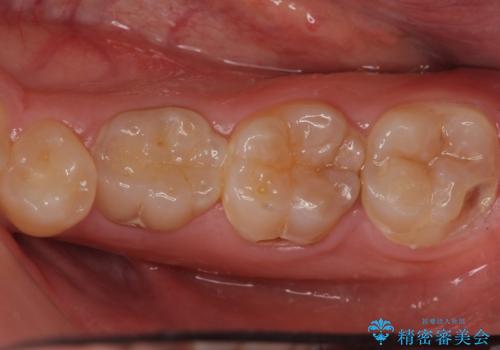

- 口の中を予算の範囲内でできるだけきれいにしたいとのことで来院された患者様です。

矯正治療と虫歯治療を組み合わせてご提案しましたが、ご予算との兼ね合いで虫歯治療のみを行うこととなりました。

奥歯は十分な歯の高さがなかったため、クラウンをかぶせる前に歯周外科治療で歯の高さを出しています。

歯科に通うようになってから磨き残しの状態も改善されていきました。